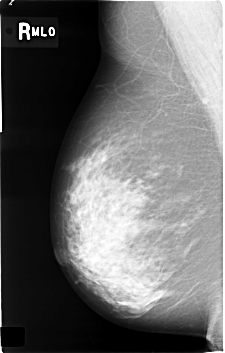

C_0362_1.RIGHT_MLO

RIGHT_MLO LINES 4584 PIXELS_PER_LINE 2920 BITS_PER_PIXEL 12 RESOLUTION 50 NON_OVERLAY